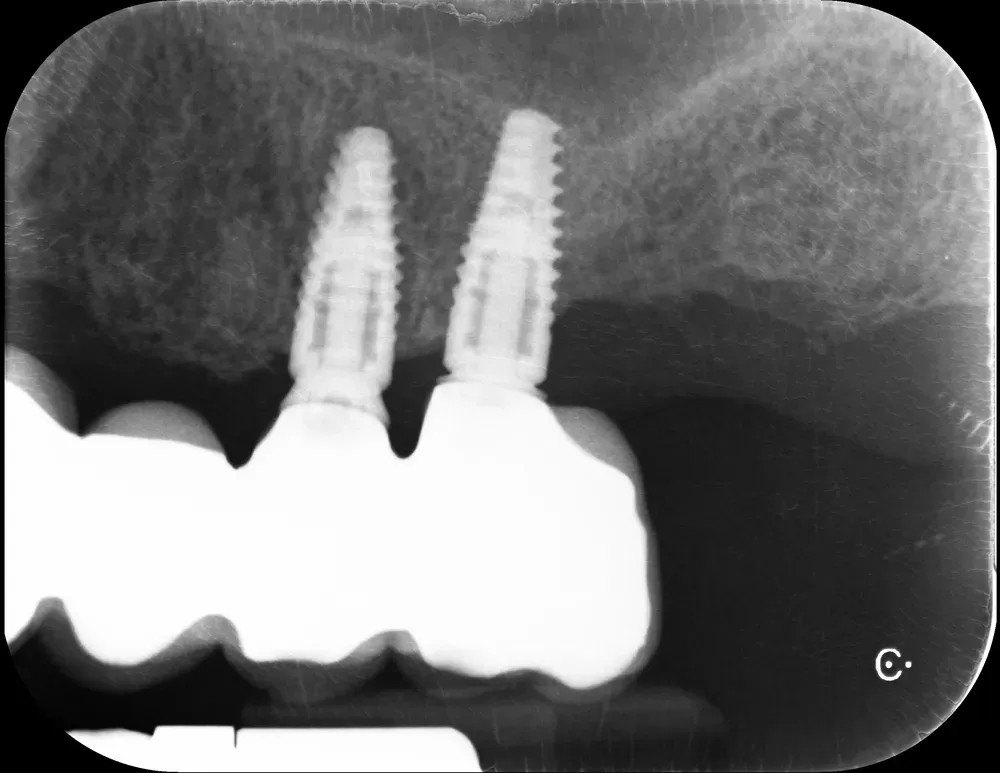

Il mascellare superiore destro era affetto da atrofia categoria S3 CCARD in posizione 16 e S2 CCARD in posizione 14 (precedentemente estratto), con presenza di cisti da ritenzione mucosa e setto di Underwood.

Inserimento impianti con rialzo del seno e aspirazione cisti da ritenzione mucosa del seno mascellare

Ho inserito due impianti, in posizione appunto 16 e 14, con minirialzo del seno mascellare e aspirazione della cisti da ritenzione mucosa tramite accesso laterale.